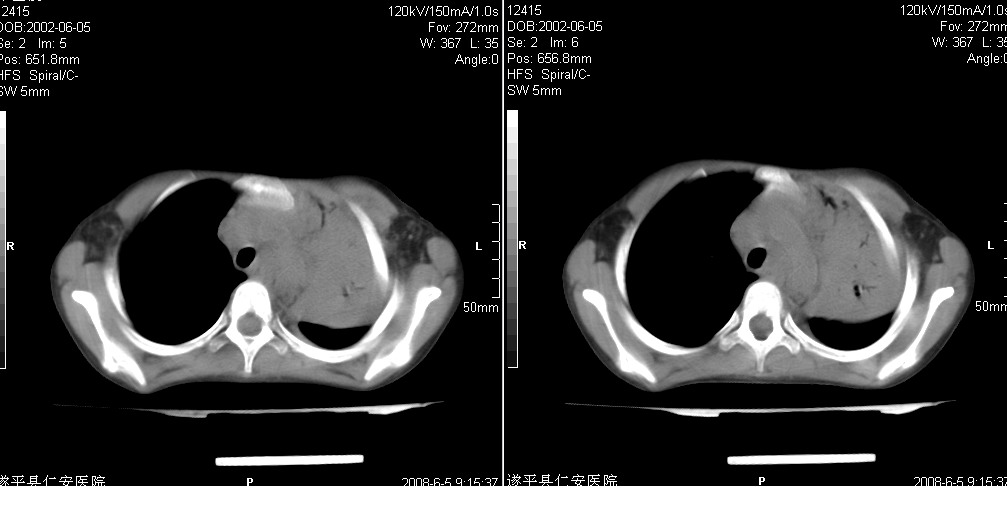

以下是引用xxhwh在2008-6-10 18:40:00的发言:[br]男,6岁,无规则发热一月余,体温在37.8——39度之间。一月前拍胸片示左上肺密度增高影,进行抗炎治疗8天,复查胸片未明显吸收。又改变抗菌素继续治疗半月,照胸片示病灶吸收不明显,行ct检查[br]征象:左上肺前段呈密实影,内可见支气管气像,远侧见絮状模糊影,中上纵隔左移。[br]意见:左上肺前段膨胀不全及感染,考虑为支气管异物或支气管内膜结核所致,[br]建议追问有无异物吸入史,行痰检及ppd检查